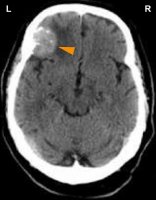

CONFLICT-ACTIVE PHASE: cell loss (necrosis) of tongue muscle tissue (controlled from the cerebral medulla) and, proportional to the degree of conflict activity, increasing paralysis of the tongue muscles (controlled from the motor cortex) affecting speech and swallowing (see also stroke and tongue paralysis). Whether the right or left side of the tongue is affected is determined by a person’s handedness and whether the conflict is mother/child or partner-related.